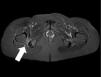

En general, se trata de roturas parciales en cualquier sitio del músculo (fig. 9). Las lesiones aisladas son poco comunes y suelen darse en deportistas de alto rendimiento (futbolistas), generalmente luego de descartar otras causas.

(a) Desgarro del obturador externo. La secuencia ponderada en STIR, plano axial, evidencia una rotura parcial a nivel de la unión miotendinosa adyacente a su inserción en el sector posterior del trocánter mayor (flecha). La consulta clínica fue por sospecha de desgarro de isquiotibiales. La ecografía resultó negativa. (b) Desgarro del obturador interno. La secuencia ponderada en T2 con supresión grasa, en plano axial, muestra una rotura fascicular (grado II) a nivel del vientre muscular con moderada cantidad de líquido y edema de partes blandas en topografía del pilar posterior del acetábulo adyacente a su inserción en el trocánter mayor (flecha).